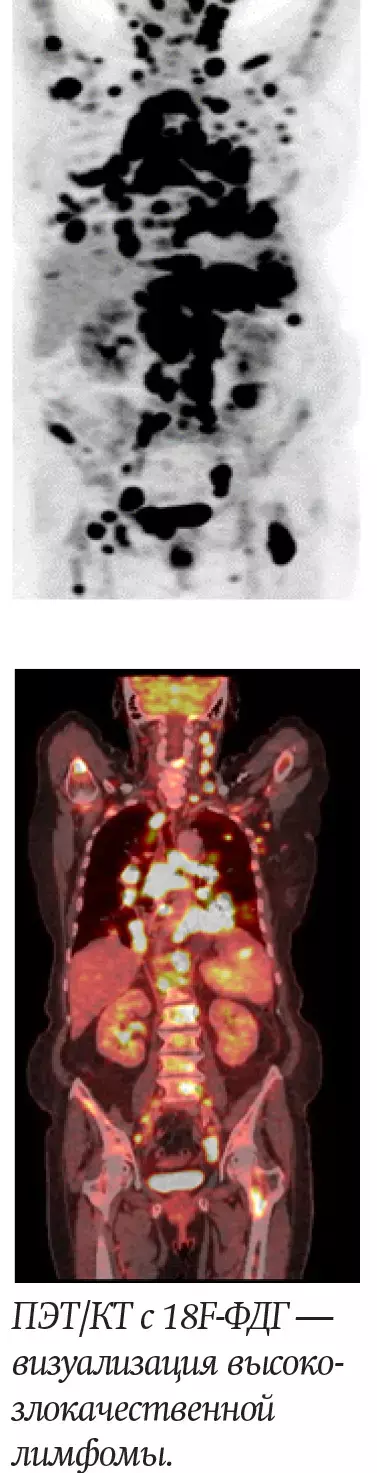

В нашей стране осуществляется радионуклидная диагностика практически всего спектра различных нозологических форм злокачественных опухолей, причем более 50 % исследований приходится на злокачественные лимфомы, рак молочной железы, рак легкого и бронхов и колоректальный рак. До настоящего времени 18F-ФДГ является самой используемой молекулой в ПЭТ/КТ-диагностике, на ее долю приходится до 90 % исследований.